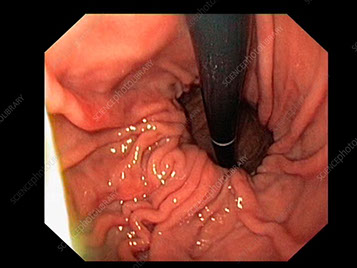

Es un exámen que permite ver directamente, desde adentro, el esófago, en estómago y el duodeno

A través de un endoscopio, se pueden introducir instrumentos pequeños y usarse para:

Mediante este estudio, se puede diagnosticar diferentes lesiones, benignas y malignas, tomar pequeñas muestras de tejido (biopsias) para analizar, sin causarle dolor, y también realizar distintos tratamientos, como sacar pólipos (lesiones como verrugas).